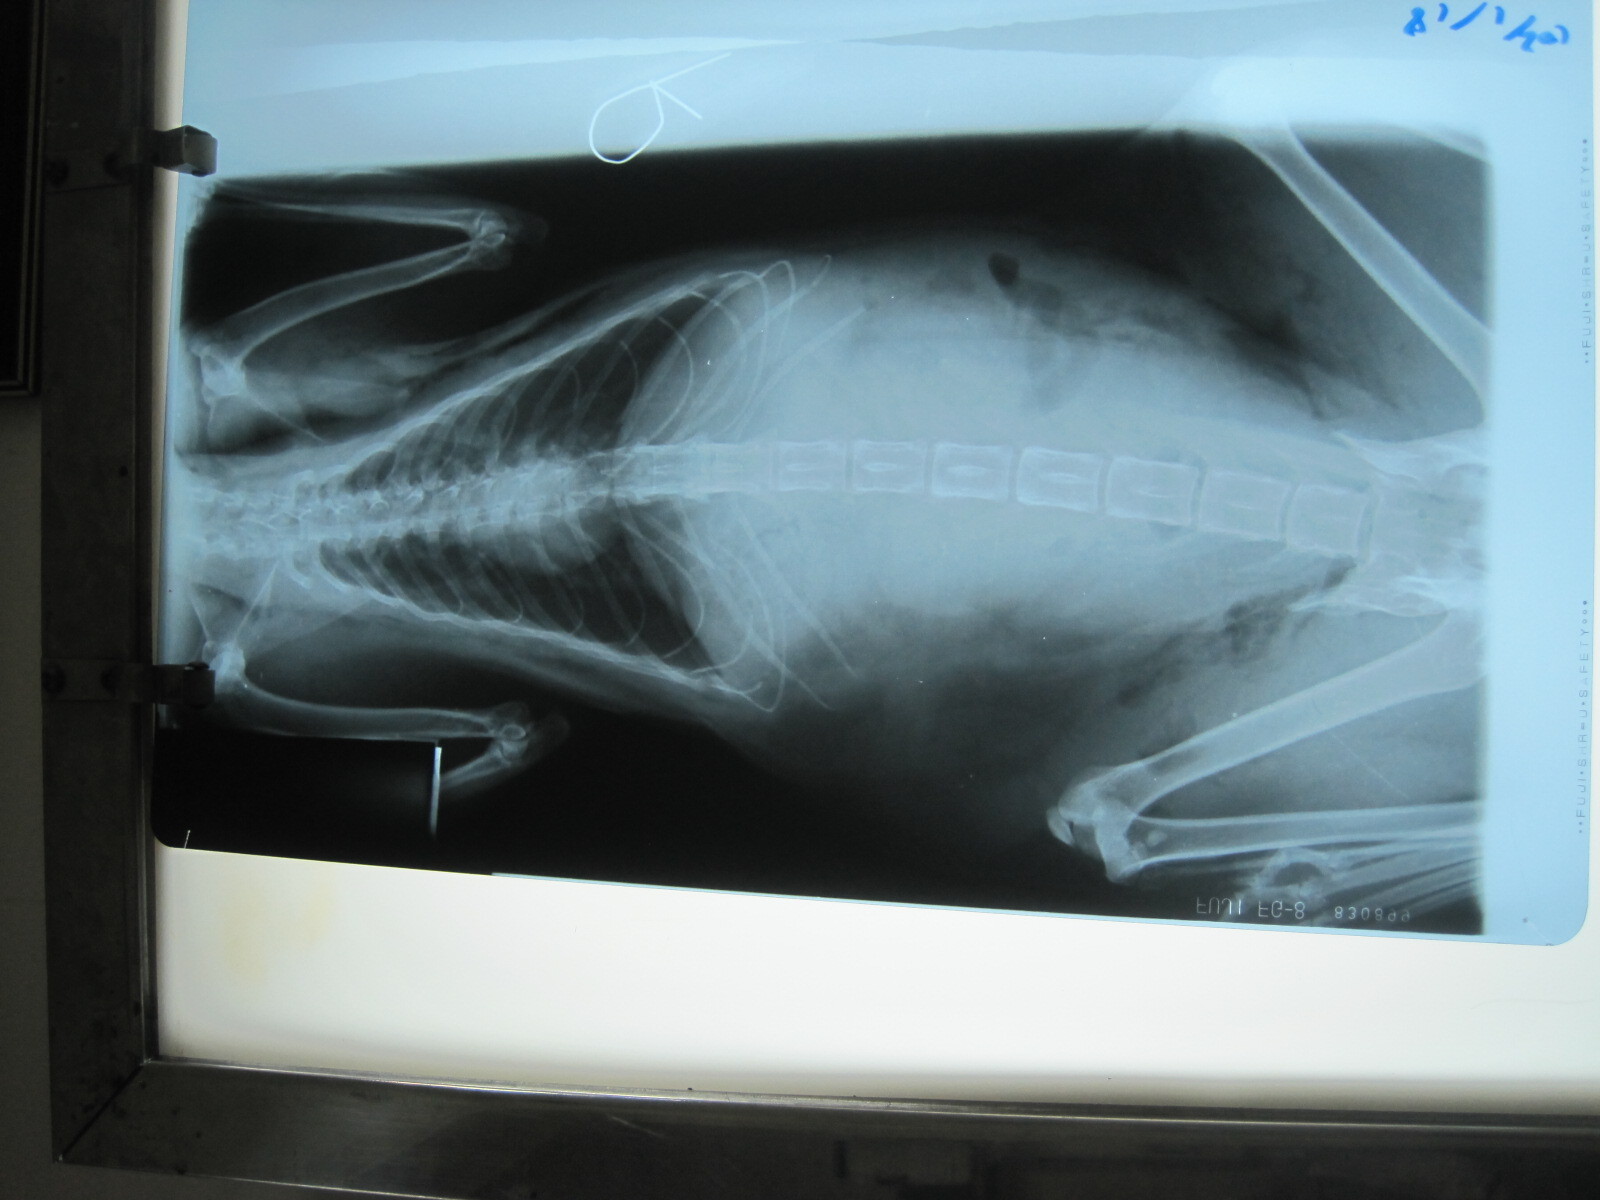

主題: 慘遭大狗咬成重傷的ㄎ一ㄎㄡㄎㄡ 申請者姓名: 張慧敏 花色: 申請日期: 2013-01-22 15:51:09 申請者部落格: 申請者臉書網址: 所在縣市/合作醫院: 台北市/詠欣動物醫院 治療費用: 5600元 需求人數: 12人 已結案 (2013-08-06 13:55:02) 報名人員: Choco Yen(已付款)、廖欣倫(已付款)、鄭古萬、Hope Liao(已付款)、Yivi Lu(已付款)、Linda(已付款)、宋小嘉(已付款)、淇勻、philip(已付款)、philip(已付款)、阿蓋 (已付款)、顏佳玲(已付款)、戴珊珊(已付款)、蔡餅乾、Shirley Tsai(已付款)、 候補人員: 動物病情說明: ㄎ一ㄎㄡㄎㄡ被大狗咬了幾口之後,已是奄奄一息,軟弱無力.鼠蹊部裂了個大洞.於是飛也似的緊急將他送醫.發現脖子附近咬了一口,氣管破了洞,有氣胸,皮下摸起來都有氣泡的感覺,腹腔也破了,一大團腸子跑到了皮下.ㄎ一ㄎㄡㄎㄡ很不舒服,血壓很低,打了好幾次才順利上點滴,緊急讓他吸氧氣和將鼠蹊部撕裂傷清乾淨和縫合.之後,住了3天的氧氣房,仍不敵死神的招喚,回天家的懷抱了.